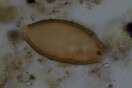

15.12.2017 Τech & Science Ανακαλύφθηκαν στην Κέα αρχαία κόπρανα με τα παρασιτικά σκουλήκια του εντέρου που περιέγραφε ο Ιπποκράτης 15.12.2017 Πρώτη φορά ανακαλύπτονται απτές ενδείξεις σε νησί του Αιγαίου γι' αυτά τα παράσιτα που αναφέρονταν στα αρχαιοελληνικά ιατρικά κείμενα